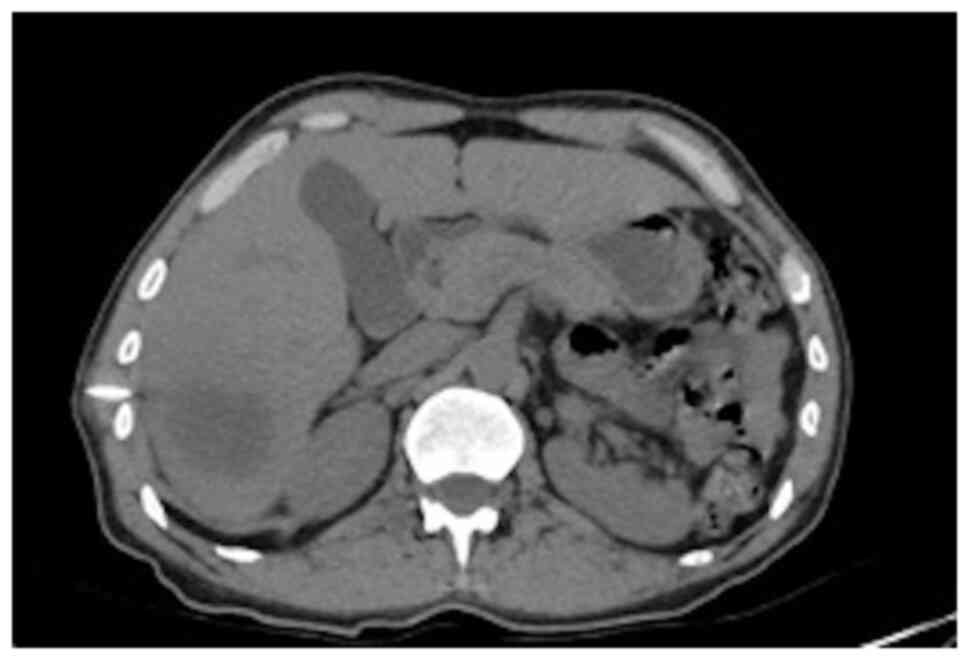

It was decided to perform PoCUS (LOGIQ e, GE Healthcare) following previously established protocols (6). A hypodense intrahepatic image was observed between segments VII and VI, with internal echoes suggestive of a liver abscess (Fig. 1). An ultrasound of the liver and bile ducts performed by a radiologist was requested. A well-defined hypodense lesion between segments VII and VI was confirmed, measuring 81x78x76 mm, with an approximate volume of 253 cc. He presented internal echoes, faint posterior acoustic enhancement and minimal perilesional vascular flow, findings that were associated with the clinical suspicion of liver abscess (Fig. 2). On the same day, radiology and general surgery were consulted. It was decided to perform tomography-guided percutaneous drainage of the liver abscess (IQon Spectral CT, Philips) following formerly recognized protocols (6). A 230 cc drainage was obtained, with no complications (Fig. 3, Fig. 4 and Fig. 5).

Figure 2

Ultrasound of the liver and bile ducts. A well-defined, hypodense lesion is observed. Gallbladder without lithiasis or dilatation of the common bile duct.